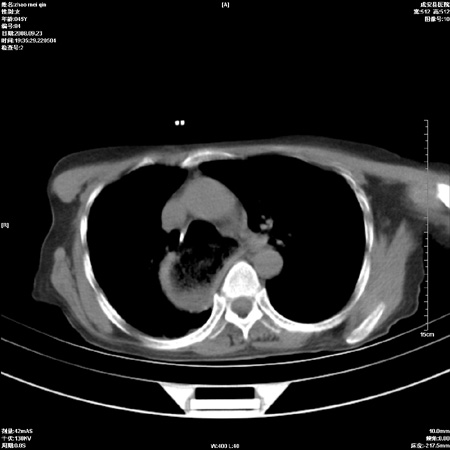

标题: CT15861:女 60 外伤后1小时 胸疼 [打印本页]

标题: CT15861:女 60 外伤后1小时 胸疼

外伤后1小时 胸疼 是外伤后引起的吗?

食道失弛缓。

未除外食道异物。如食道石长时间受阻。

不除外贲门占位梗阻

非外伤性改变,典型的贲门失迟缓症